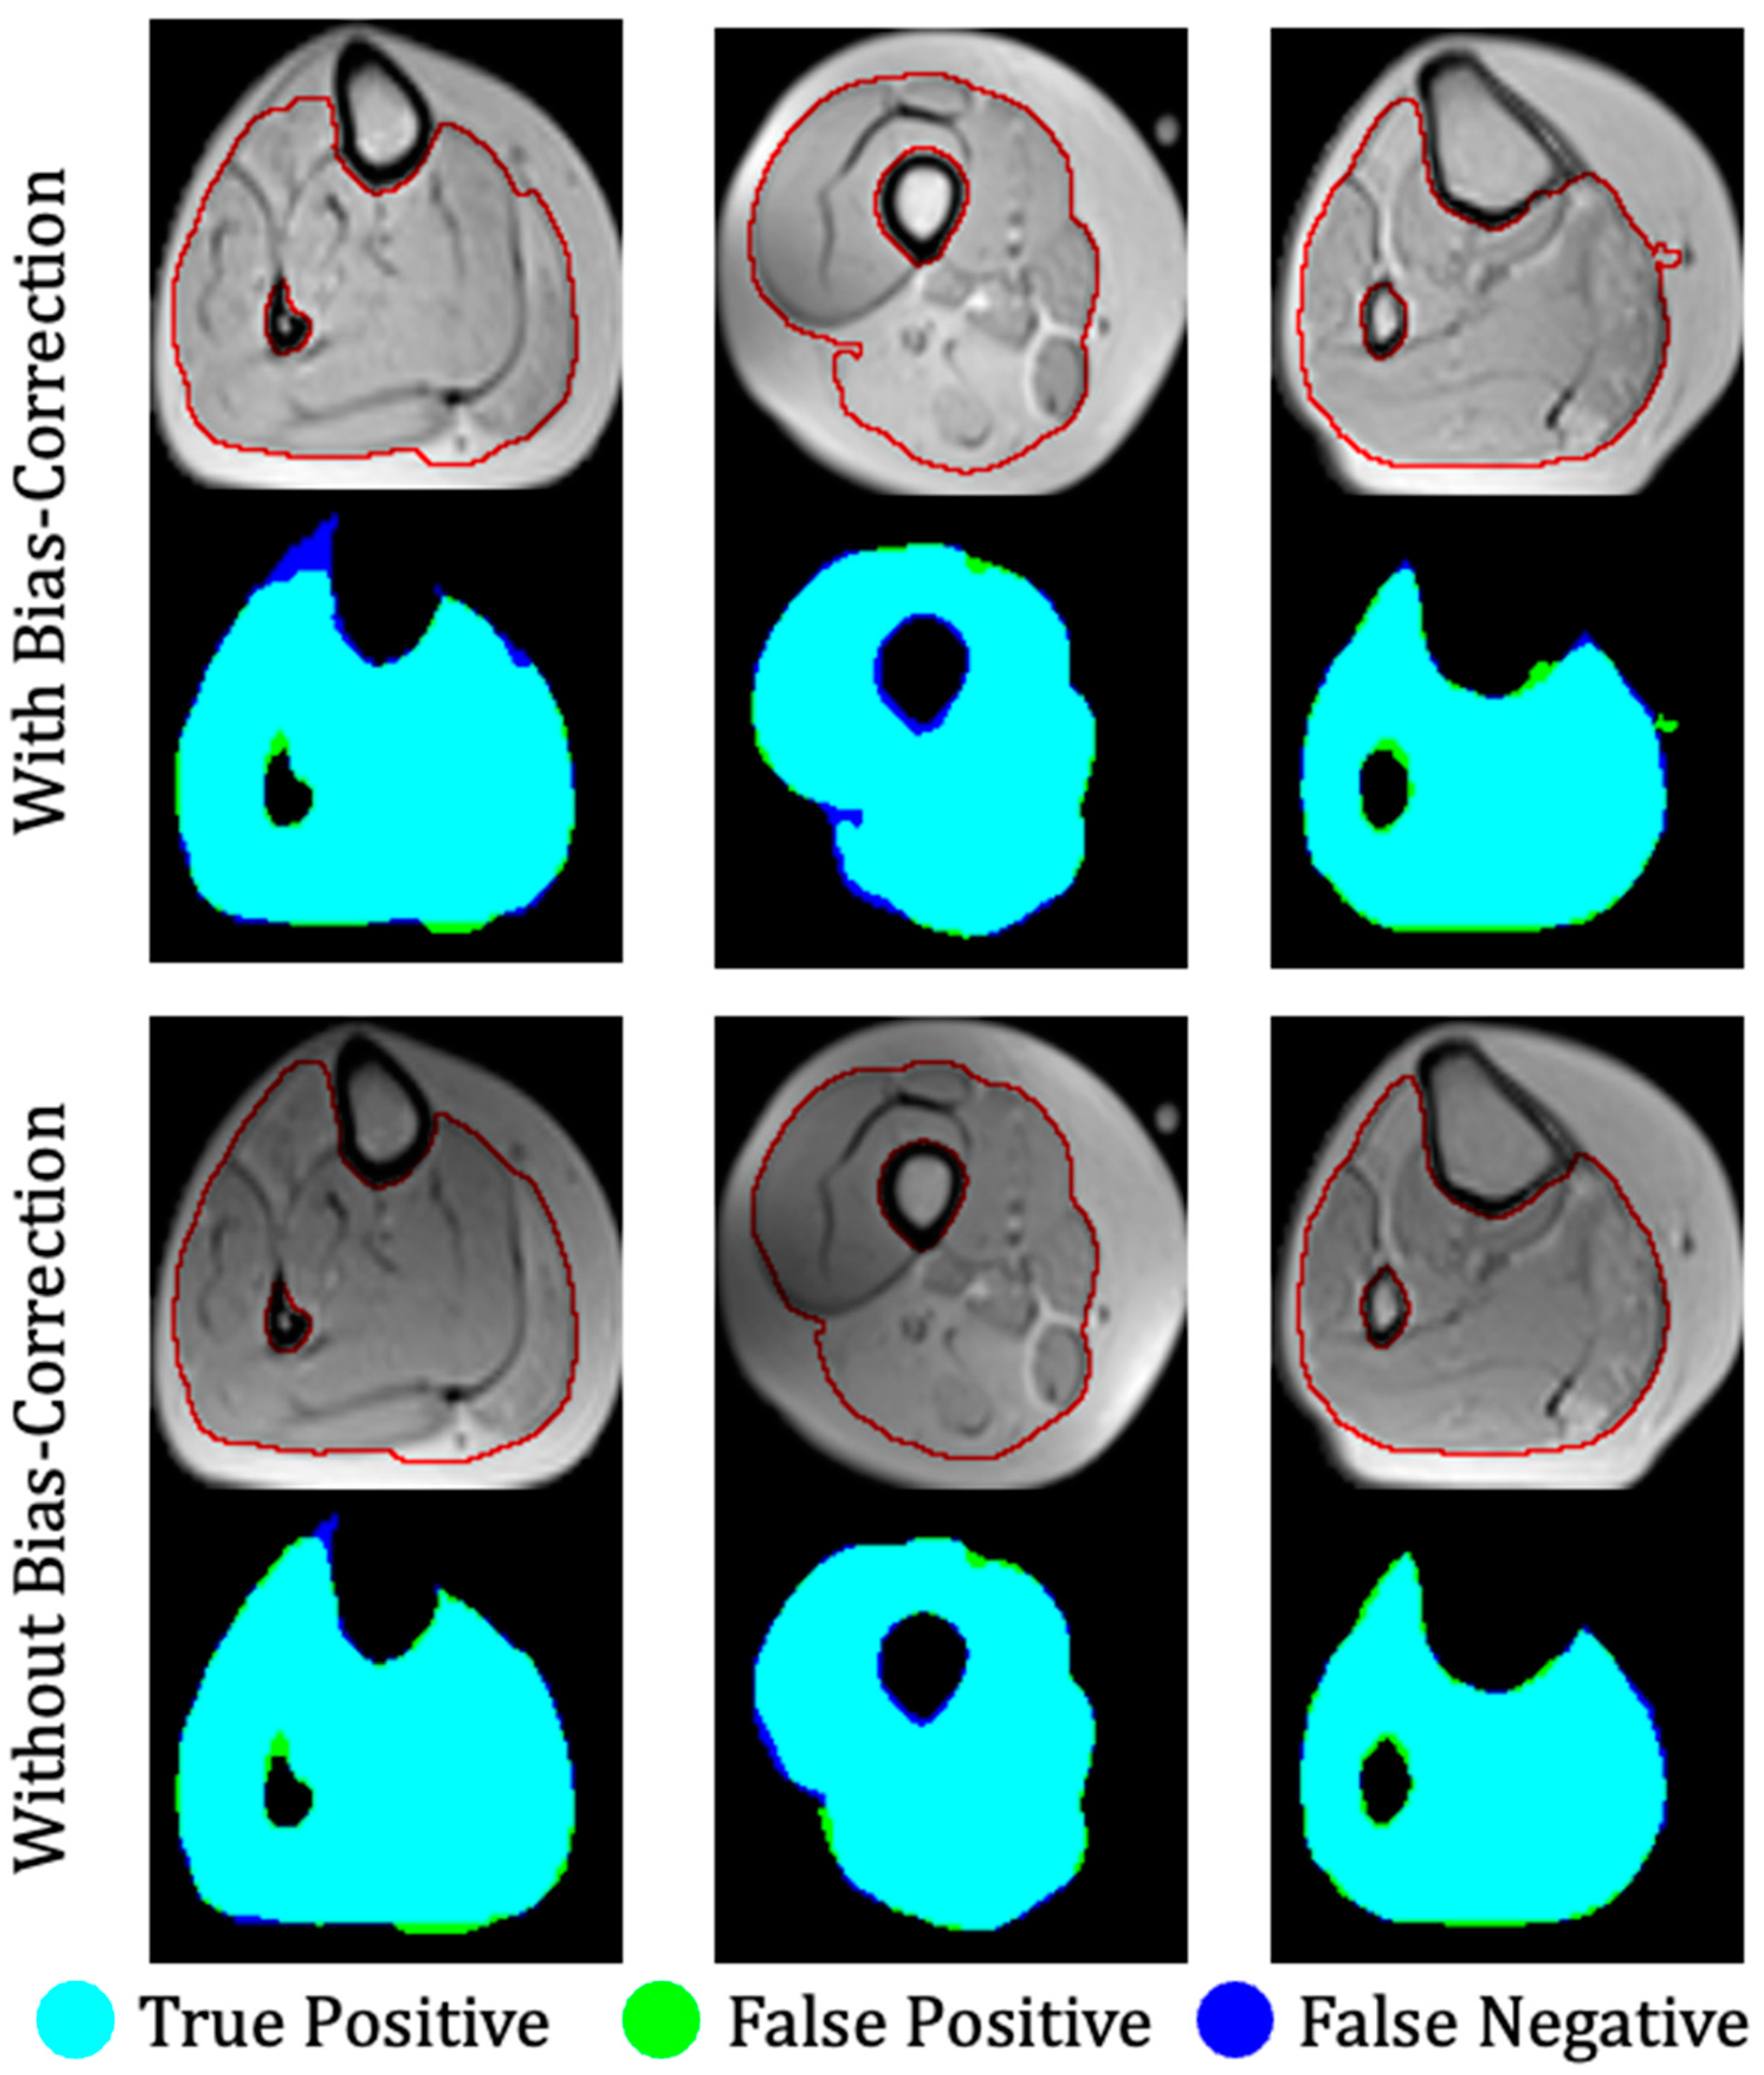

Muscle dystrophies (MDs) are an inherited class of disorders characterized by progressive muscle weakness that affects the upper and lower limbs, the axial muscles, and the facial muscles at variable levels of severity. Fat infiltration into muscles of the lower limbs is one of the hallmarks of these diseases’ progression and can be easily seen in MRI images. MDs lead to a loss of muscle mass and a weakening of muscle strength [1]. The infiltrated fat is usually referred to as intermuscular adipose tissue (IMAT) and is separated from the subcutaneous adipose tissue (SAT), which surrounds the muscle. The two fat tissues are separated by a boundary layer called “fascia lata”, used in many studies to achieve reliable segmentation of the lower limb anatomy (see Figure 1).

Figure 1. Axial MR image of the thigh. Red: fascia lata boundary; blue, green, and yellow arrows mark the subcutaneous fat, a region of viable muscle, and IMAT pixels.

Figure 7. Three examples of segmentation of a calf anatomy. Left to right: mild, moderate, and severe levels of fat infiltration. Top: With bias field correction; bottom: without bias field correction. Manual segmentation contours are shown in red. Overlap between ground truth and the output of the fully convolutional network is color-coded to indicate regions of true positive, false positive, and false negative segmentation.